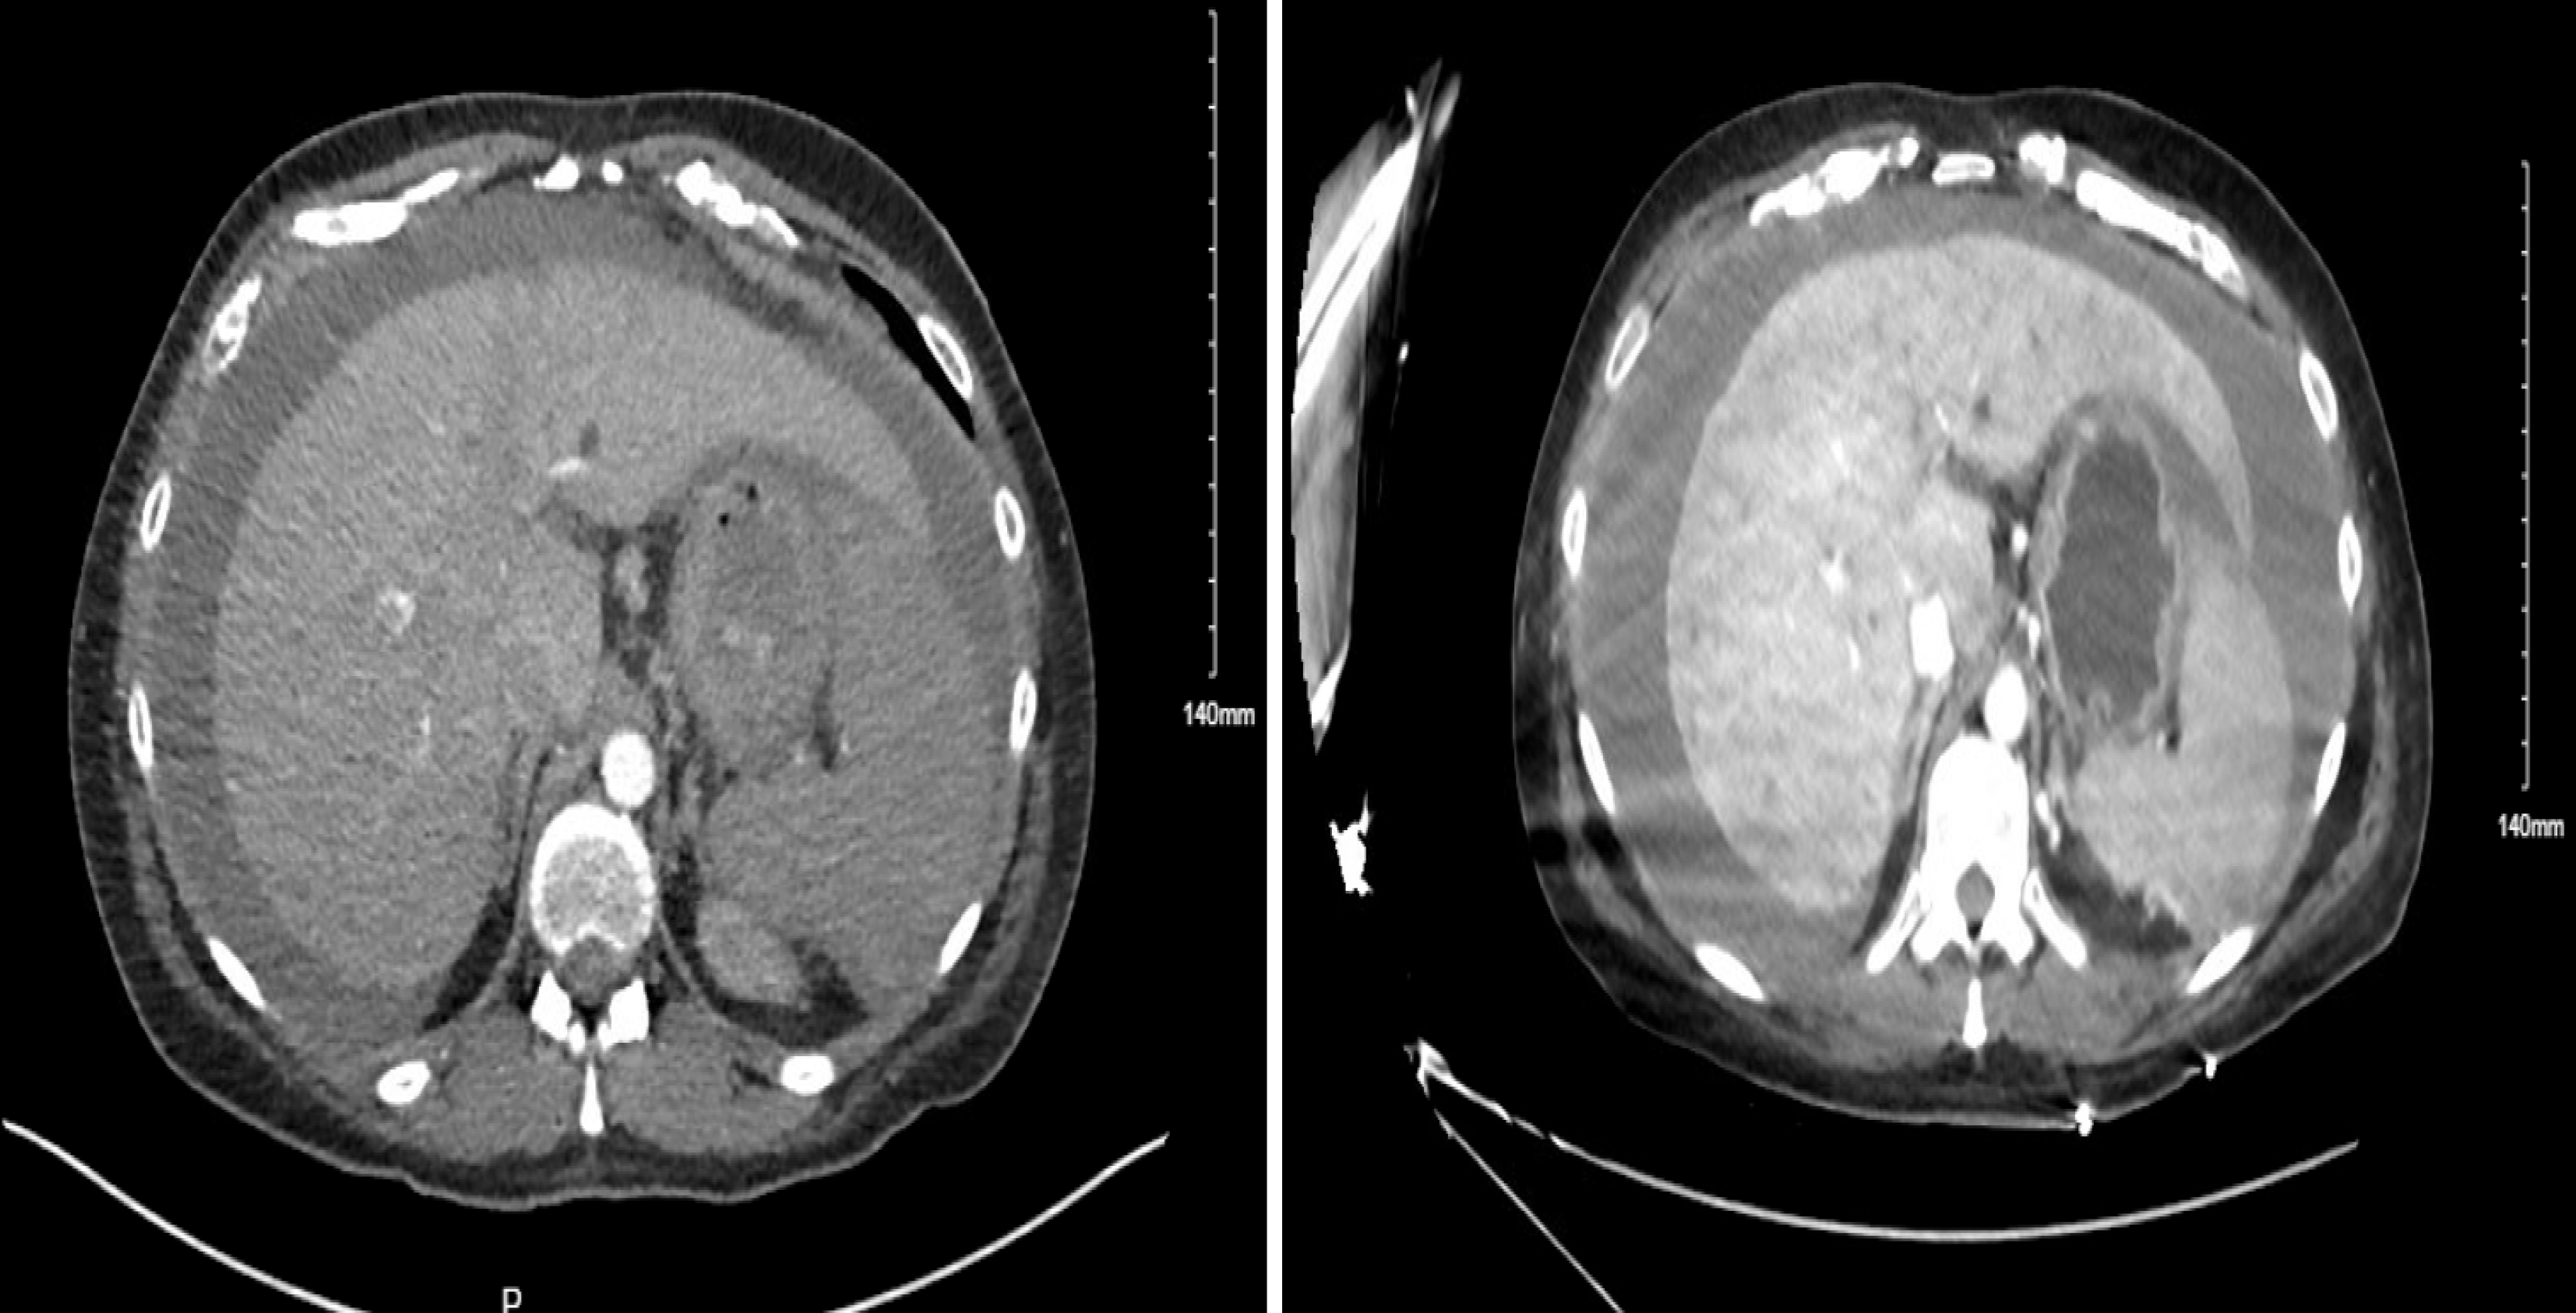

Figure 1 Left image showing initial computed tomography angiography abdomen/pelvis prior to transfer demonstrating hemoperi toneum.

Right image showing repeat computed tomography angiography abdomen pelvis approximately eight hours later showing stable large volume hemoperitoneum.